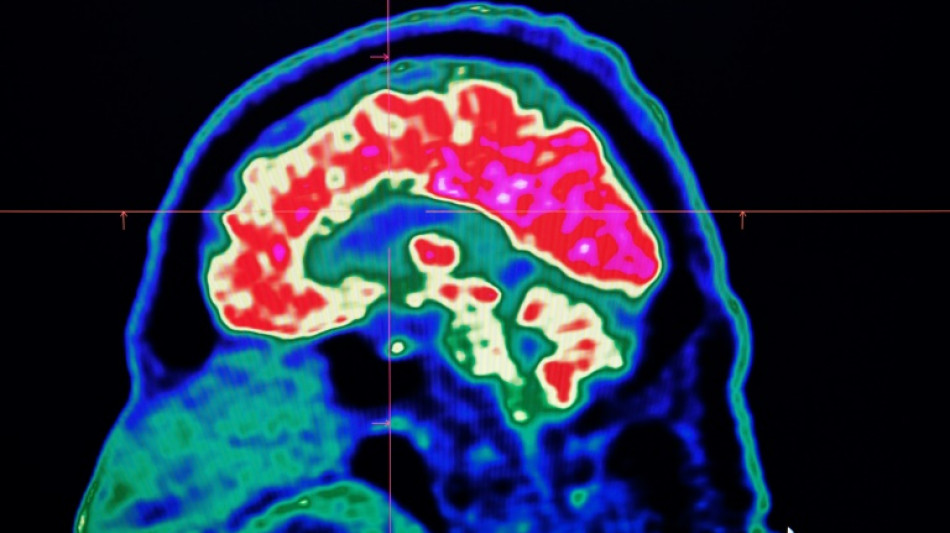

Surging nervous system disorders now top cause of illness: study / Photo: Fred TANNEAU - AFP/File

Conditions affecting the nervous system -- such as strokes, migraines and dementia -- have surged past heart disease to become the leading cause of ill health worldwide, a major new analysis said on Friday.

More than 3.4 billion people -- 43 percent of the global population -- experienced a neurological condition in 2021, far more than had previously been thought, the analysis found.

Lead study author Jaimie Steinmetz of the IHME said the results showed that nervous system conditions are now "the world's leading cause of overall disease burden".